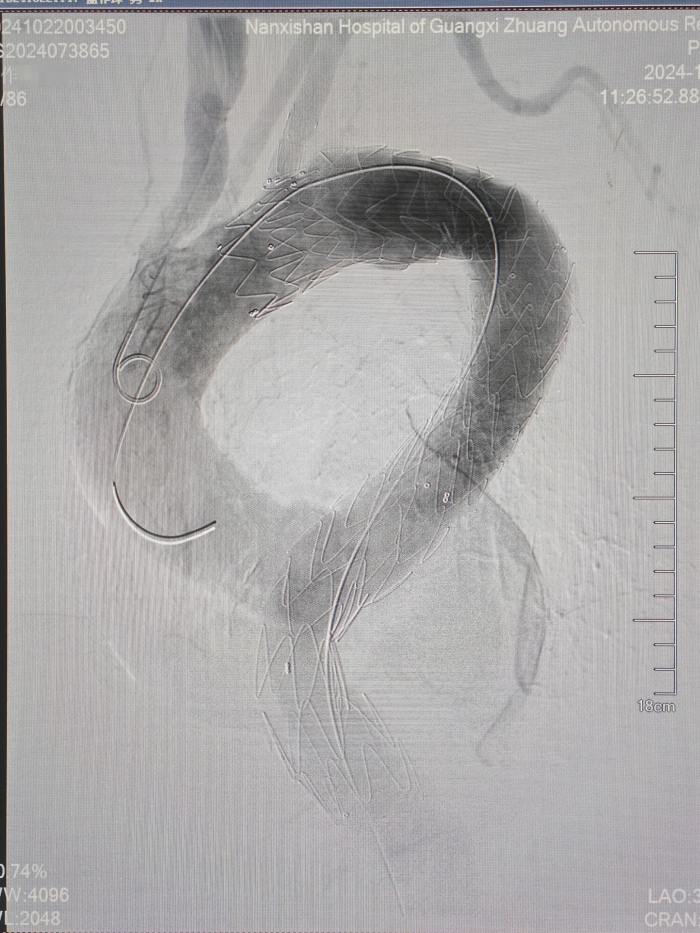

胸主动脉支架植入术后

冠脉支架前后

首先,医生们为患者进行了全麻下分支型胸主动脉覆膜支架腔内隔绝术。由于动脉瘤瘤体直径较大且累及范围较长,一个分支型覆膜支架无法完全覆盖瘤腔,于是在远端又接入了一个直筒支架。复查造影显示动脉瘤隔绝良好、无内漏,手术效果达到预期,“排雷”成功!

随后,在心血管内科屈妍副主任医师的会诊协助下,医生们进一步为患者进行了冠脉造影检查,发现冠脉三支病变,其中右冠开口处重度狭窄。于是同期植入了一枚冠脉支架,成功疏通了冠脉血管,“通路”畅通无阻。